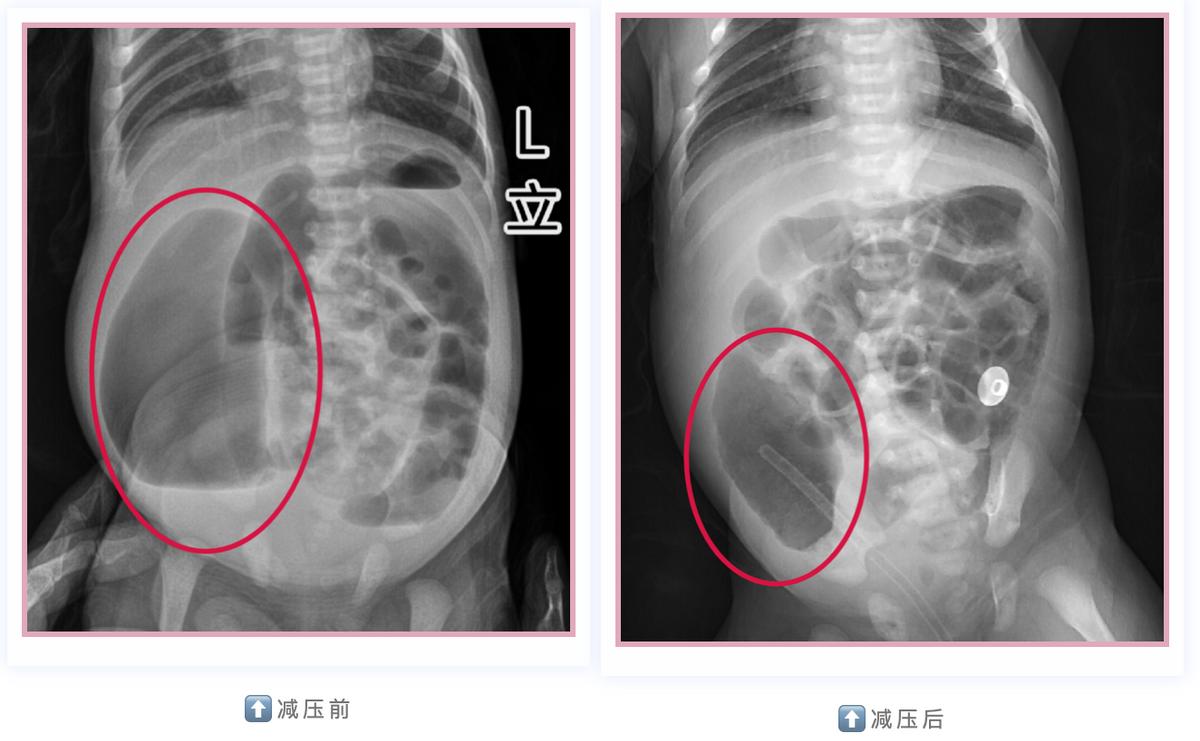

面对小宝凶险万分的病情,对小儿外科疑难危重病人的诊治、抢救有着丰富经验的周小渔教授当机立断,尝试从小宝的瘘口插管进行减压。随着小宝肠道内的气体和其他内容物从管道排出,再结合检查结果,周小渔教授松了一口气: 小宝不需要进行风险更高的急诊手术了,可以安心待到术前检查完善后再择期手术。